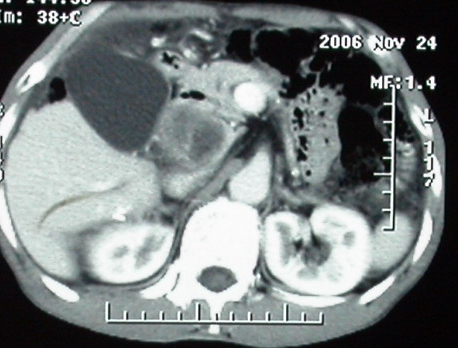

补充一点重要资料:今日查afp大于正常值10倍以上。因此,本病例最大可能应该是肝癌。

手术结果:

肝脏尾状叶肝癌(沿肝十二指肠韧带向下韧带内生长,门腔间隙外压增大),大结节性肝硬化,胆囊积脓,胆道感染。术中见肝外胆道2cm直径,肿瘤向前压迫胆管至扁平状态。